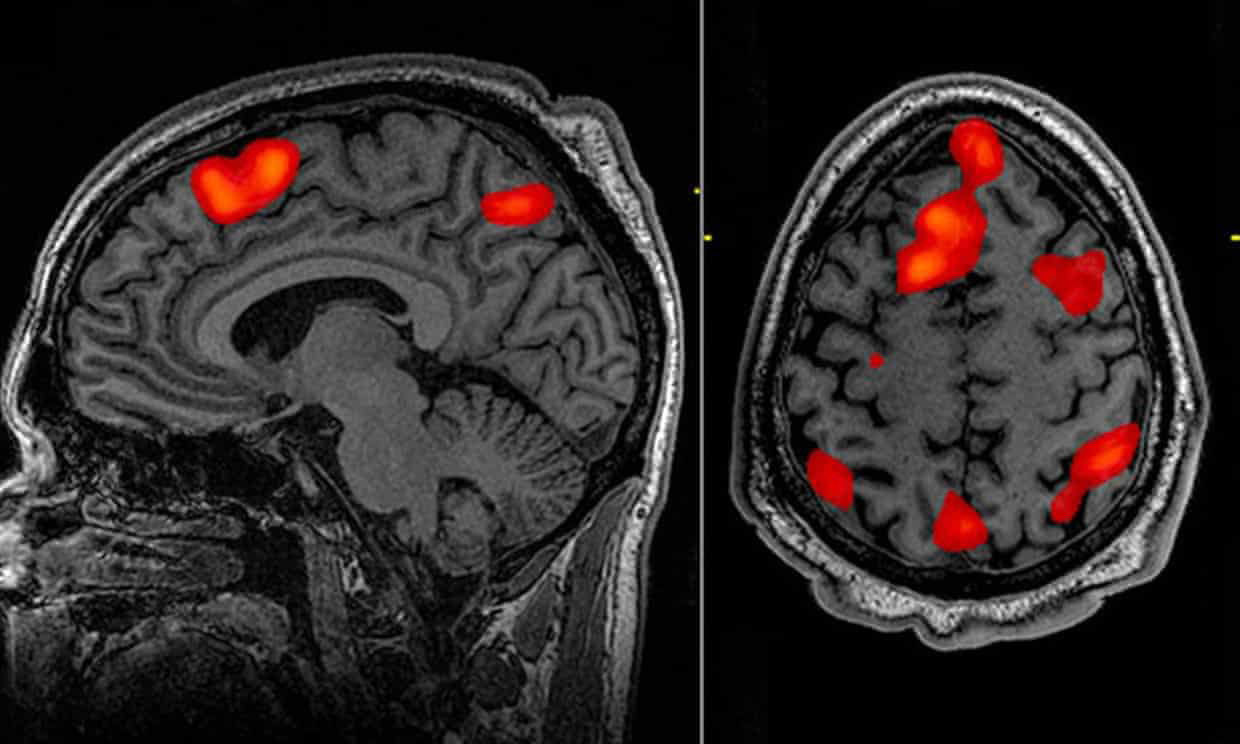

A kutatók szerint a dekóder kizárólag fMRI-olvasás adatai alapján kivételes pontossággal képes rekonstruálni azt a beszédet, amit az alanyok pusztán csak elképzeltek, de sosem mondták ki hangosan szavakkal. Az eszköz azért jelent óriási áttörést, mert az ehhez hasonló nyelvi dekóderek sebészeti úton behelyezett implantátumokkal működnek. Az új módszerrel viszont már nem lesz szükség műtétre ahhoz, hogy segítsen visszaállítani a nyelvi kommunikációt a stroke vagy motoros neuronbetegséggel küzdőknek.

Három önkéntesnek egyenként 16 órán át kellett egy szkennerben feküdnie, és podcastokat hallgatnia. Később ugyanezeket a résztvevőket egy új anyag hallgatása vagy egy történet elképzelése közben szkennelték, miközben a dekóder pusztán az agyi aktivitásuk alapján próbálta rekonstruálni ezeket a szöveget.

Ilyen agyi aktivitásokat fejti vissza az AI